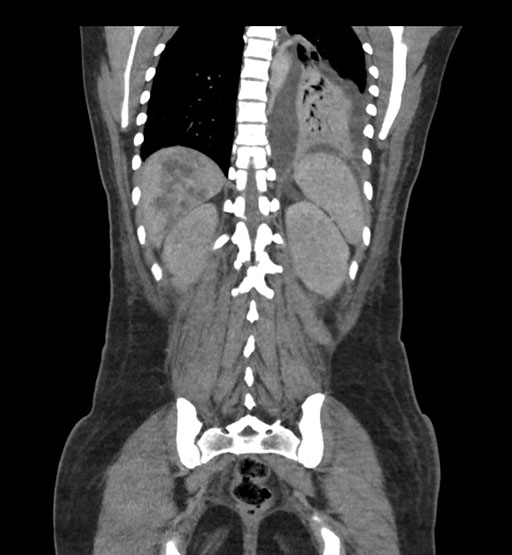

Coronal Arterial

Imaging analysis

Based on initial findings, which issue(s) would you be most concerned about?